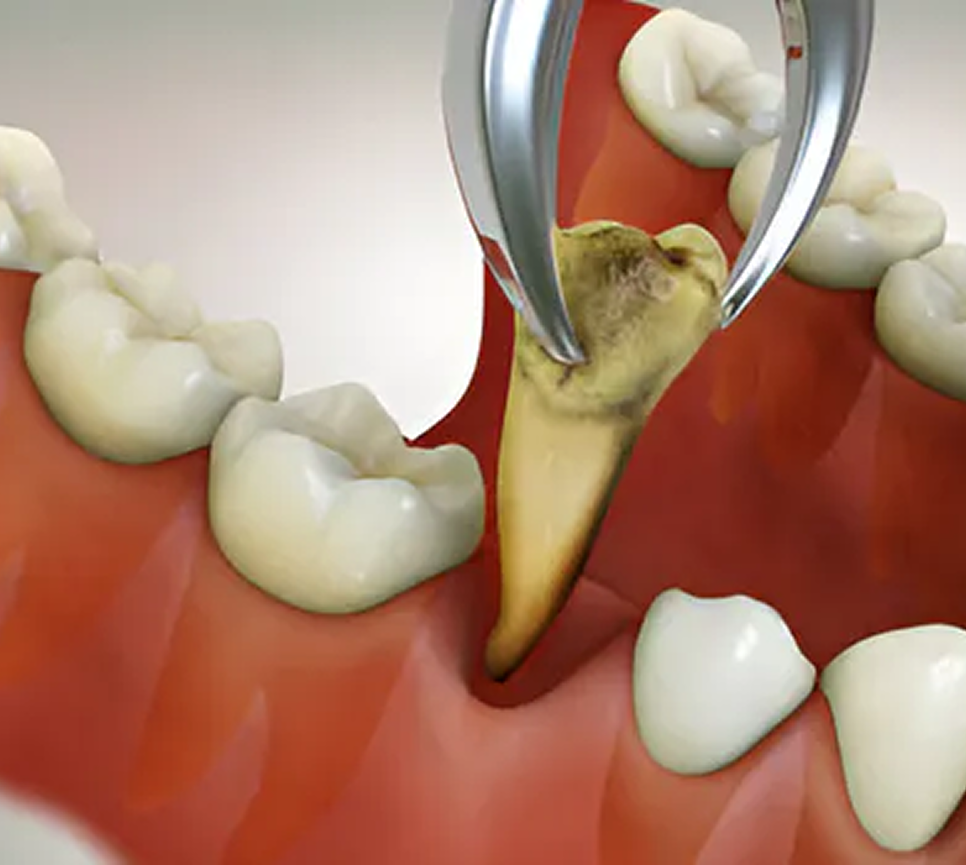

Implant & Restorative Dentistry

From preventive care to advanced dental treatments, we provide comprehensive solutions tailored for children, adults, and seniors.

From general and preventive dentistry to cosmetic, orthodontic, and advanced restorative treatments, we offer comprehensive dental solutions for patients of all age groups.